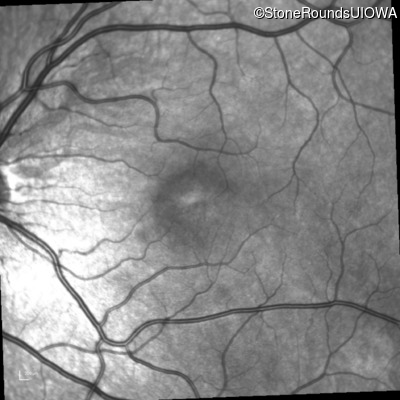

This 6 year old boy first experienced difficulty reading and seeing the blackboard at age 5.

Diagnosis & molecular findings

| XL Retinoschisis | RS1 | Pro192His CCC>CAC | XL |